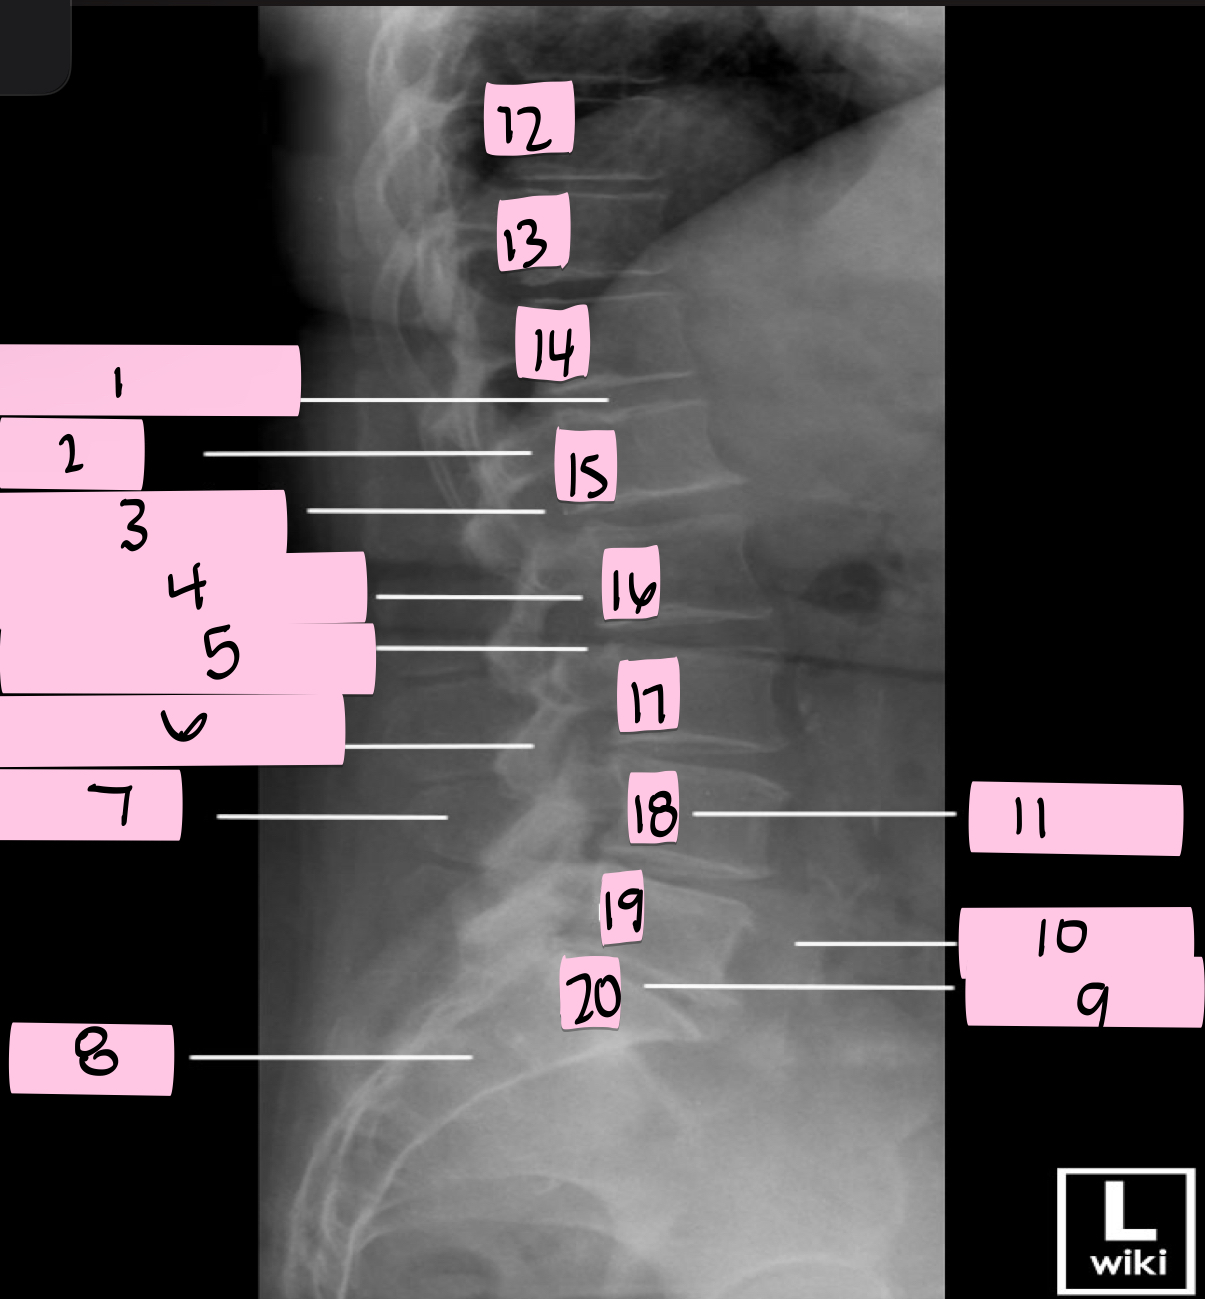

What is 1 pointing to?

Intervertebral disk

What is 2 pointing to?

Pedicle

What is 3 pointing to?

Intervertebral foramen

What is 4 pointing to?

Inferior vertebral notch

What is 5 pointing to?

Superior vertebral notch

What is 6 pointing to?

Inferior articular process

What is 7 pointing to?

Spinous process

What is 8 pointing to?

Sacrum

What is 9 pointing to?

L5 S1 joint

What is 10 pointing to?

Iliac crest

What is 11 pointing to?

Vertebral body (L4)

What is 12 pointing to?

T10

What is 13 pointing to?

T11

What is 14 pointing to?

T12

What is 15 pointing to?

L1

What is 16 pointing to?

L2

What is 17 pointing to?

L3

What is 18 pointing to?

L4

What is 19 pointing to?

L5

What is 20 pointing to?

S1